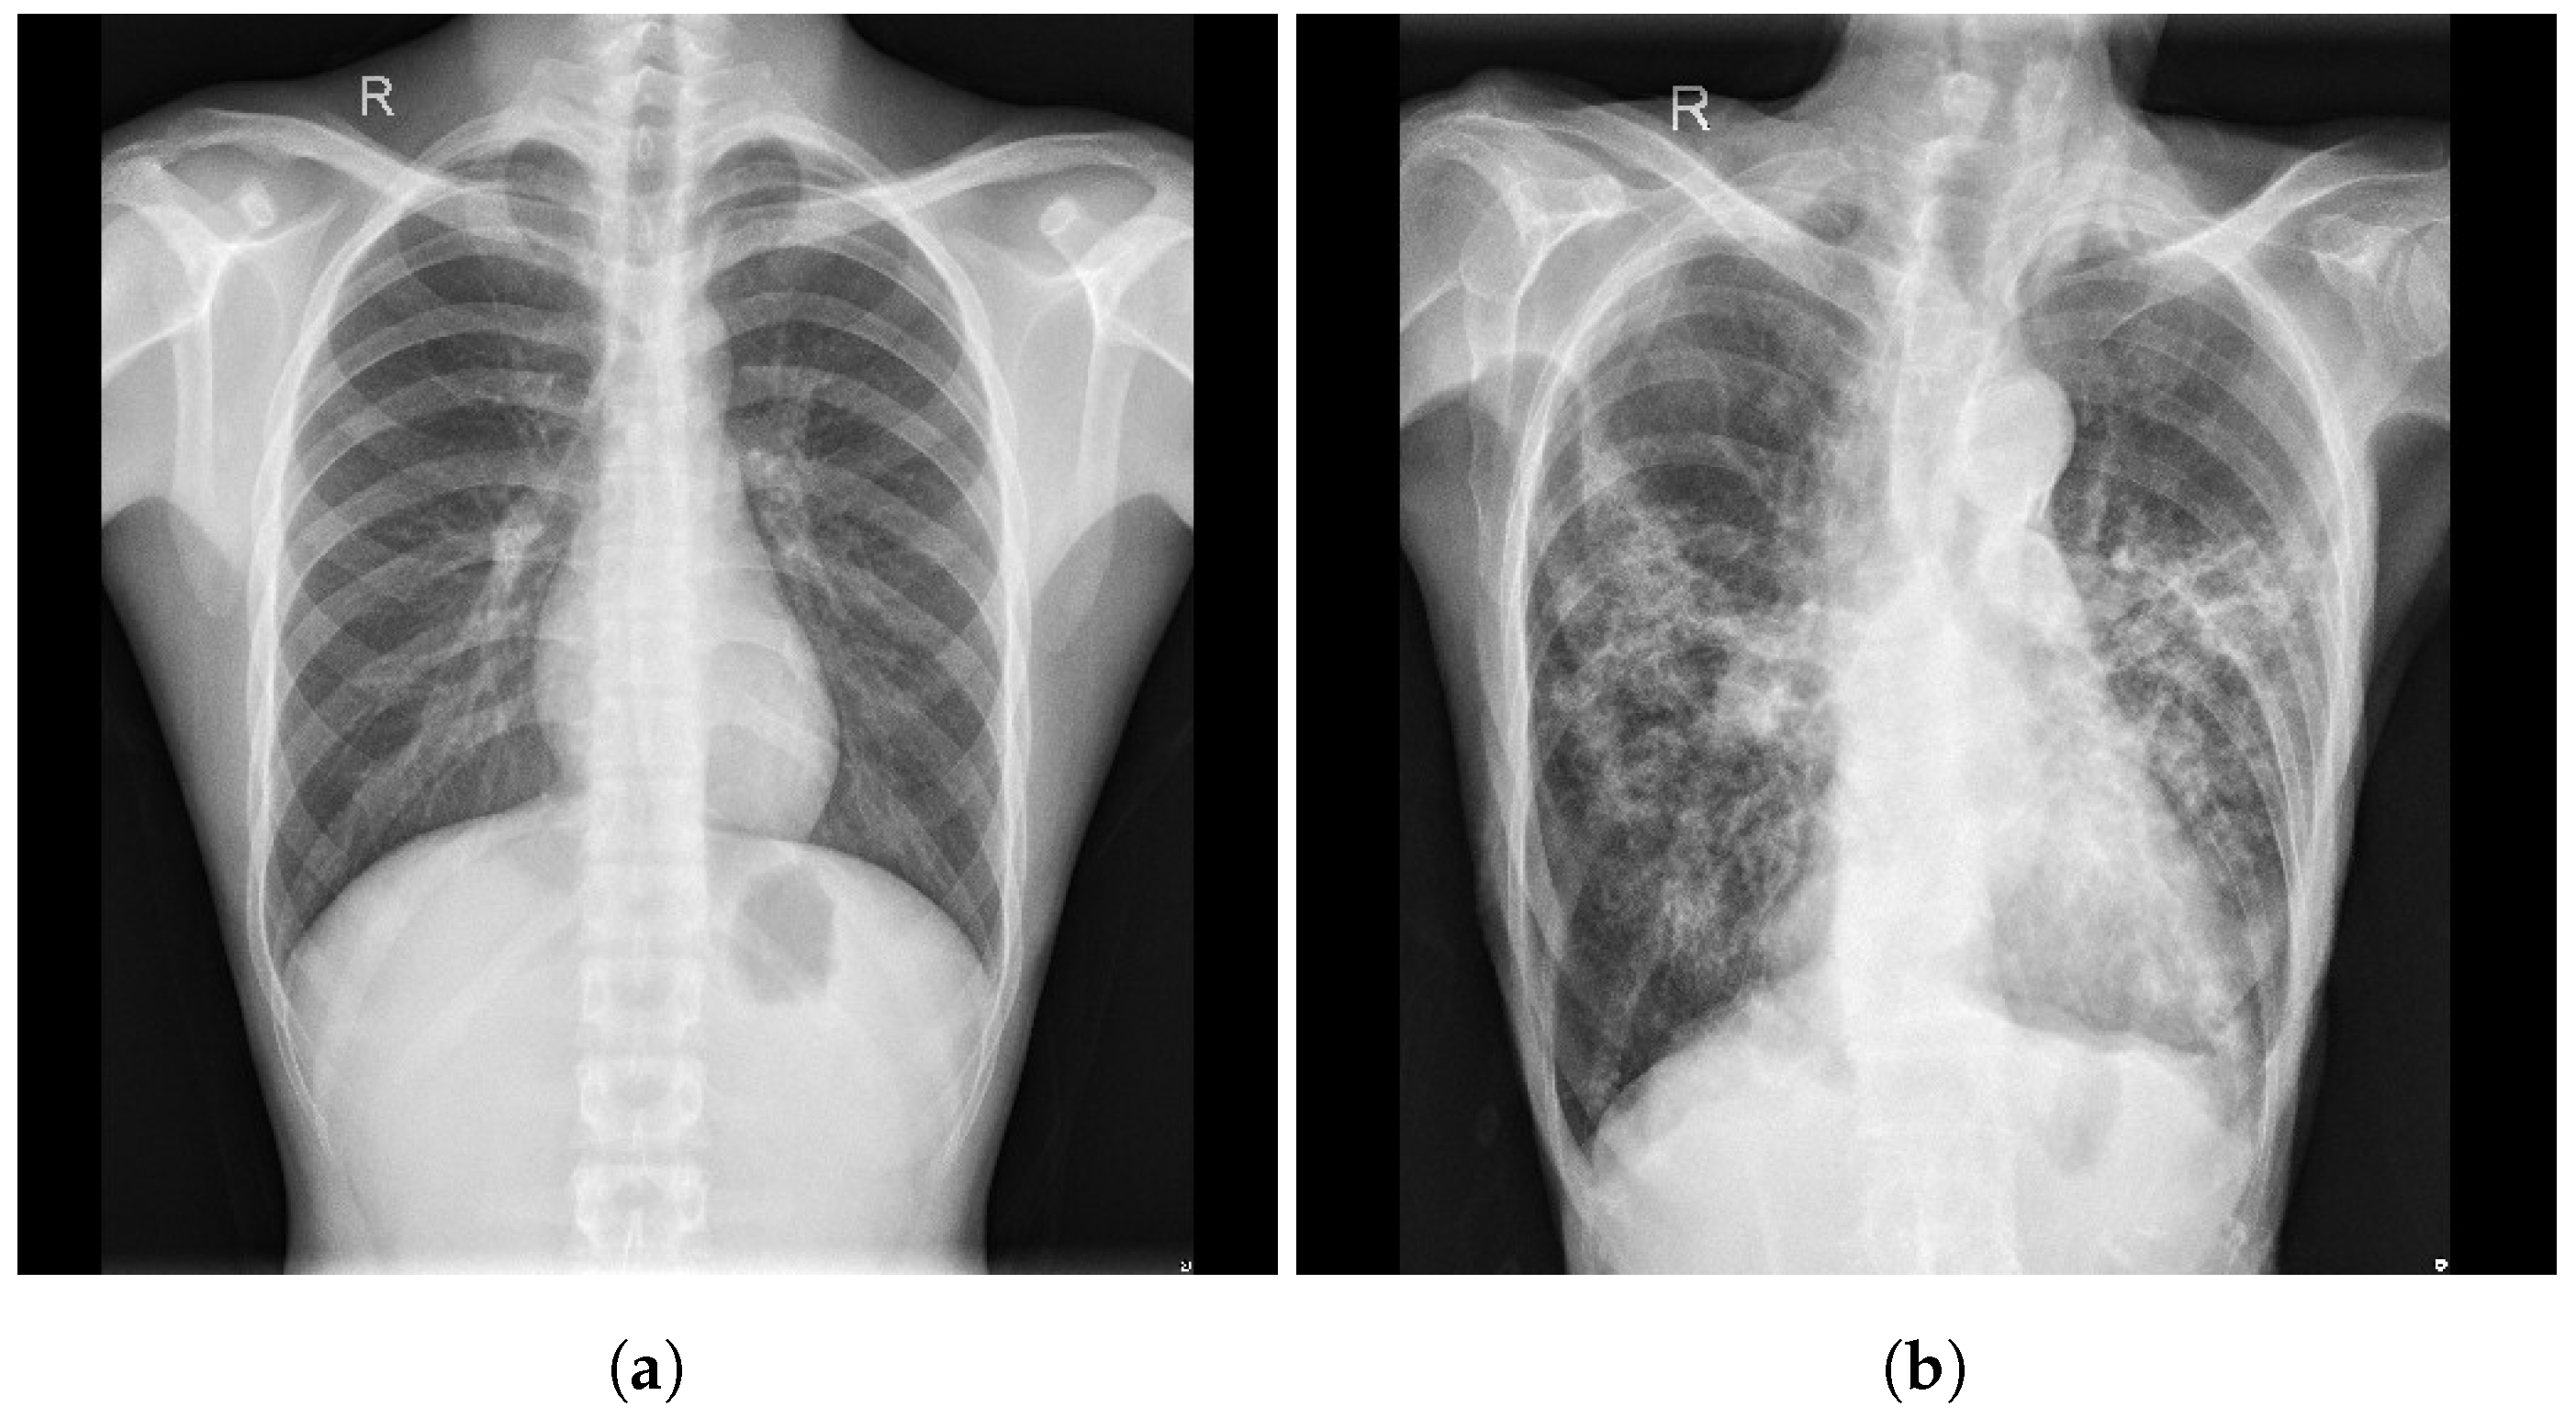

3.1. COVID-19 Image Data Collection (CIDC)

3.2. COVID-19 Radiography

3.3. BIMCV COVID19+